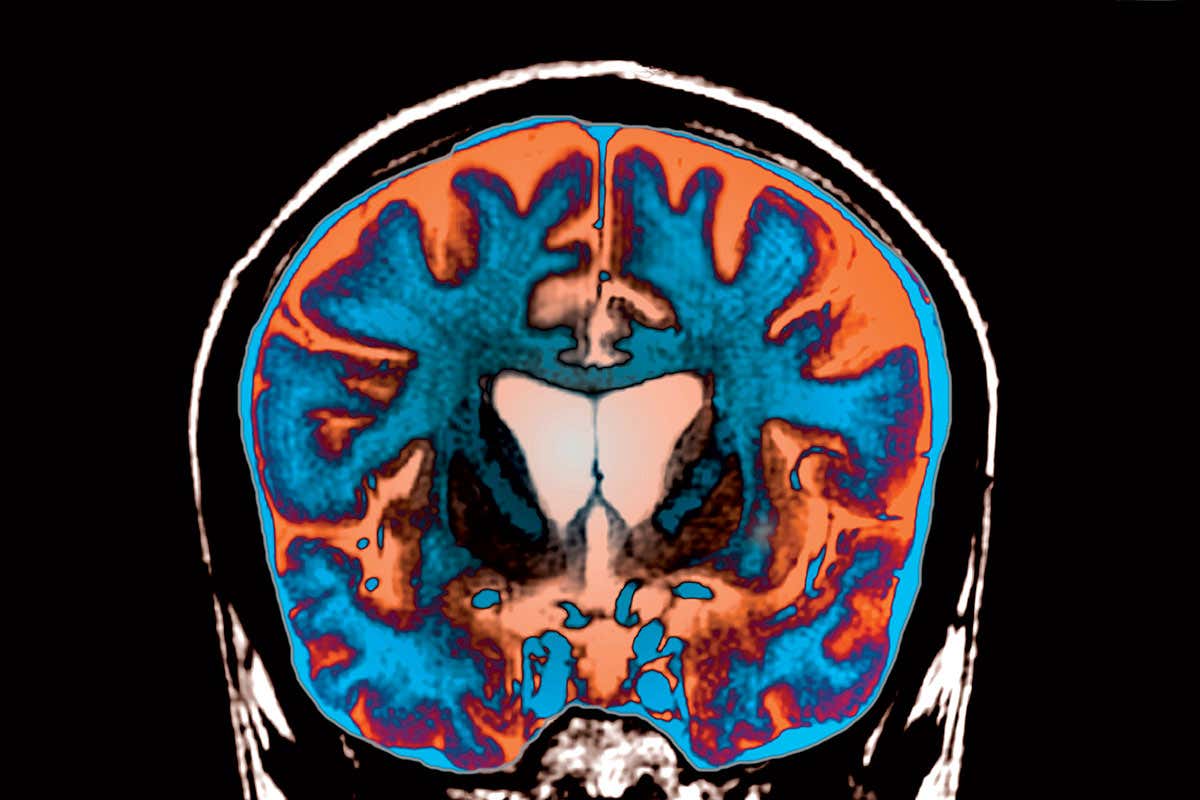

Next on the list:Huntington’s ZEPHYR/SCIENCE PHOTO LIBRARY

The full results haven’t yet been published, but what has been revealed so far of this “antisense” therapy suggests we have overcome the biggest obstacle – how to deliver such therapies – at least in disorders that affect the nervous system. The breakthrough could open the floodgates for similar treatments for neurological conditions such as Huntington’s, motor neurone disease and possibly even Alzheimer’s.